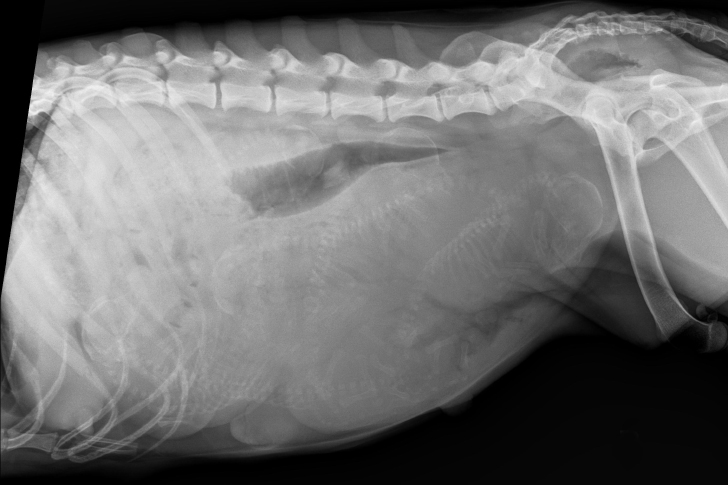

A glance at the morning radiographs told a fuller story than the belly alone. Spines and skulls overlapped like a string of beads, crowding space. The veterinarian felt the clock stretch in his mind, the shape of a long day forming. He met the owner’s eyes and explained gently that a large litter was likely to occur.